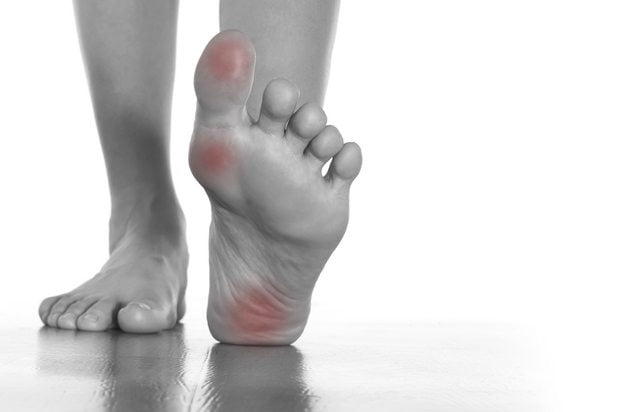

На развитие патологии указывает появление болезненности чаще раза в неделю, постепенное повышение ее интенсивности. Косвенными признаками воспалительного или деструктивного процесса становятся отечность и покраснение кожи над суставом, его тугоподвижность.

Характер болей

Дергающая, пульсирующая боль в пальце указывает на острое течение воспалительного процесса. Сопутствующими симптомами практически всегда являются покраснение, разглаживание, отечность кожи. Мелкие кровеносные сосуды переполняются кровью, поэтому большой палец стопы становится горячим на ощупь. Все эти признаки характерны для следующих патологий:

- подагры;

- инфекционного, ревматоидного, реактивного артрита;

- тендинита, тендовагинита.

Резкая пронизывающая боль возникает в момент травмирования сустава — перелома, вывиха, ушиба после падения или направленного удара. Слабые дискомфортные ощущения в большом пальце ноги — один из симптомов развивающегося артроза, деформирующего остеоартроза или остеопороза. Их выраженность повышается постепенно и через несколько месяцев или лет боли в суставе становятся постоянными.